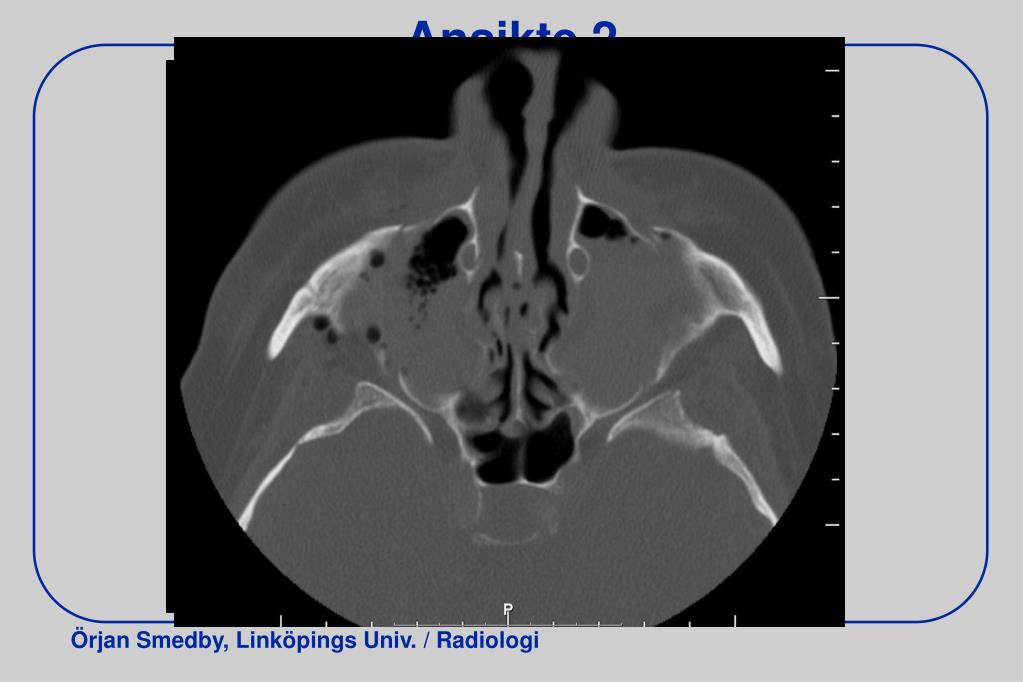

32. Ansikte 2

33. Ansikte 2 - cor

34. Ansikte 2 – VRT